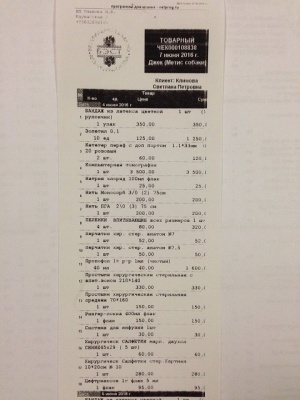

– салфетка стерильная марлевая 16 см х 14 см (33,95 руб.), салфетка стерильная марлевая 45 см х 29 см 4 шт. (155,20 руб.), бинт стерильный 7м х 14 см 7 шт. (169,75 руб.), хлоргексидина биглюконат раствор водный х 10 шт. (88,75 руб.) согласно листу назначений от 04.06.2016 (чек, товарный чек 2) - 447,65 руб.;

– окончательная оплата за проведение компьютерной томографии правого скакательного сустава (КТ) врач Горшков Сергей Сергеевич, и операции (снятие пластины) хирург Козлов Евгений Матвеевич, клиника Бэст (чек 3, товарный чек 3, лист назначений – документ 3) – 7756 руб.;

– салфетка стерильная марлевая 16 см х 14 см (33,95 руб.), салфетка стерильная марлевая 45 см х 29 см 4 шт. (155,20 руб.), бинт стерильный 7м х 14 см 7 шт. (169,75 руб.), хлоргексидина биглюконат раствор водный х 10 шт. (88,75 руб.) согласно листу назначений от 04.06.2016 (чек, товарный чек 2) - 447,65 руб.;

– окончательная оплата за проведение компьютерной томографии правого скакательного сустава (КТ) врач Горшков Сергей Сергеевич, и операции (снятие пластины) хирург Козлов Евгений Матвеевич, клиника Бэст (чек 3, товарный чек 3, лист назначений – документ 3) – 7756 руб.;

Лист приема и назначений от 15.06.2016, итоговый чек за период 02.03.2016 - 07.06.2016.